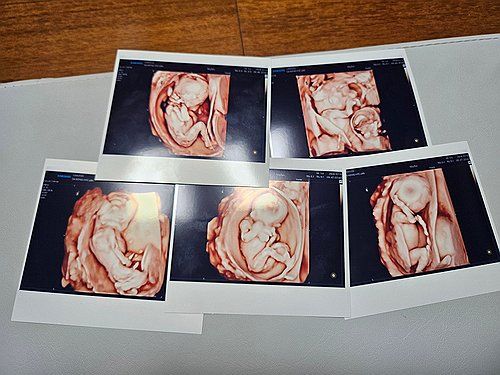

(서울=연합뉴스) 서울성모병원은 9월 20일 낮 남자아이 3명과 여자아이 2명의 '오둥이'가 건강하게 태어났다고 밝혔다. 사진은 오둥이의 초음파 사진. [서울성모병원 제공. 재판매 및 DB 금지] photo@yna.co.kr